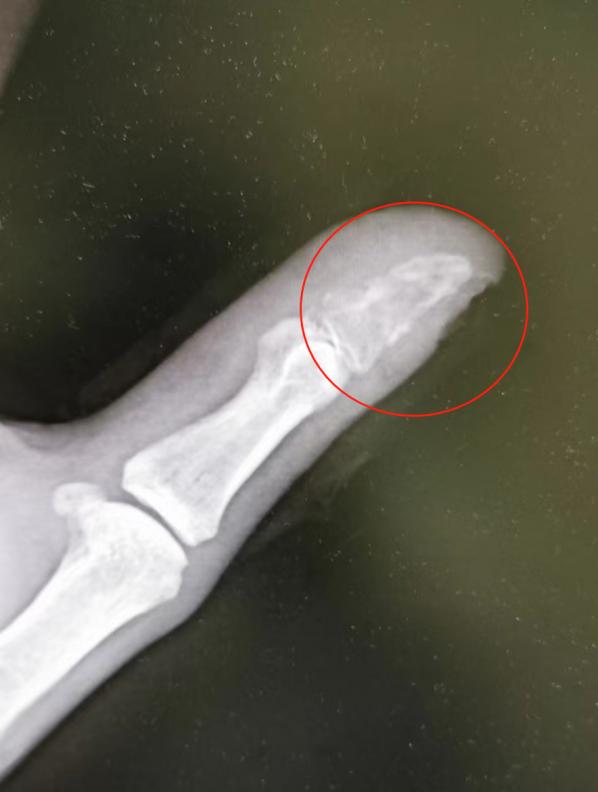

患者拇指末节指骨被细菌侵蚀“吃空”。

一周后,蒋先生发现手指伤口红肿,便到附近医院就诊。医生发现蒋先生伤口有感染,为其清创换药,并叮嘱他按时到医院换药,但怕麻烦的蒋先生一去不返,继续在家自行消毒处理。5月底,蒋先生不仅伤口没长好,手指还疼得不敢触碰,这才来到武汉市第四医院手外科门诊。经检查,蒋先生伤口感染严重,拍片显示拇指末节指骨也被细菌侵蚀“吃空”,存在截指的风险。